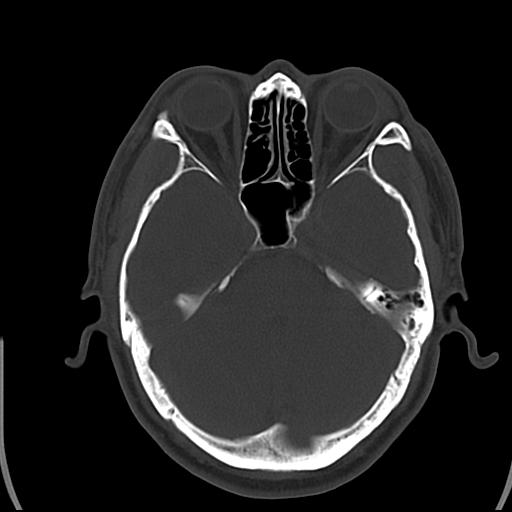

头皮下高密度结节影???临床上在老年男性比较常见。大家看看是什么?成因是? 本例患者,男性,51岁。外伤来诊。无染发史及发根植入史。

皮下钙化点

没见过,可能为毛囊钙化。

考虑钙化。